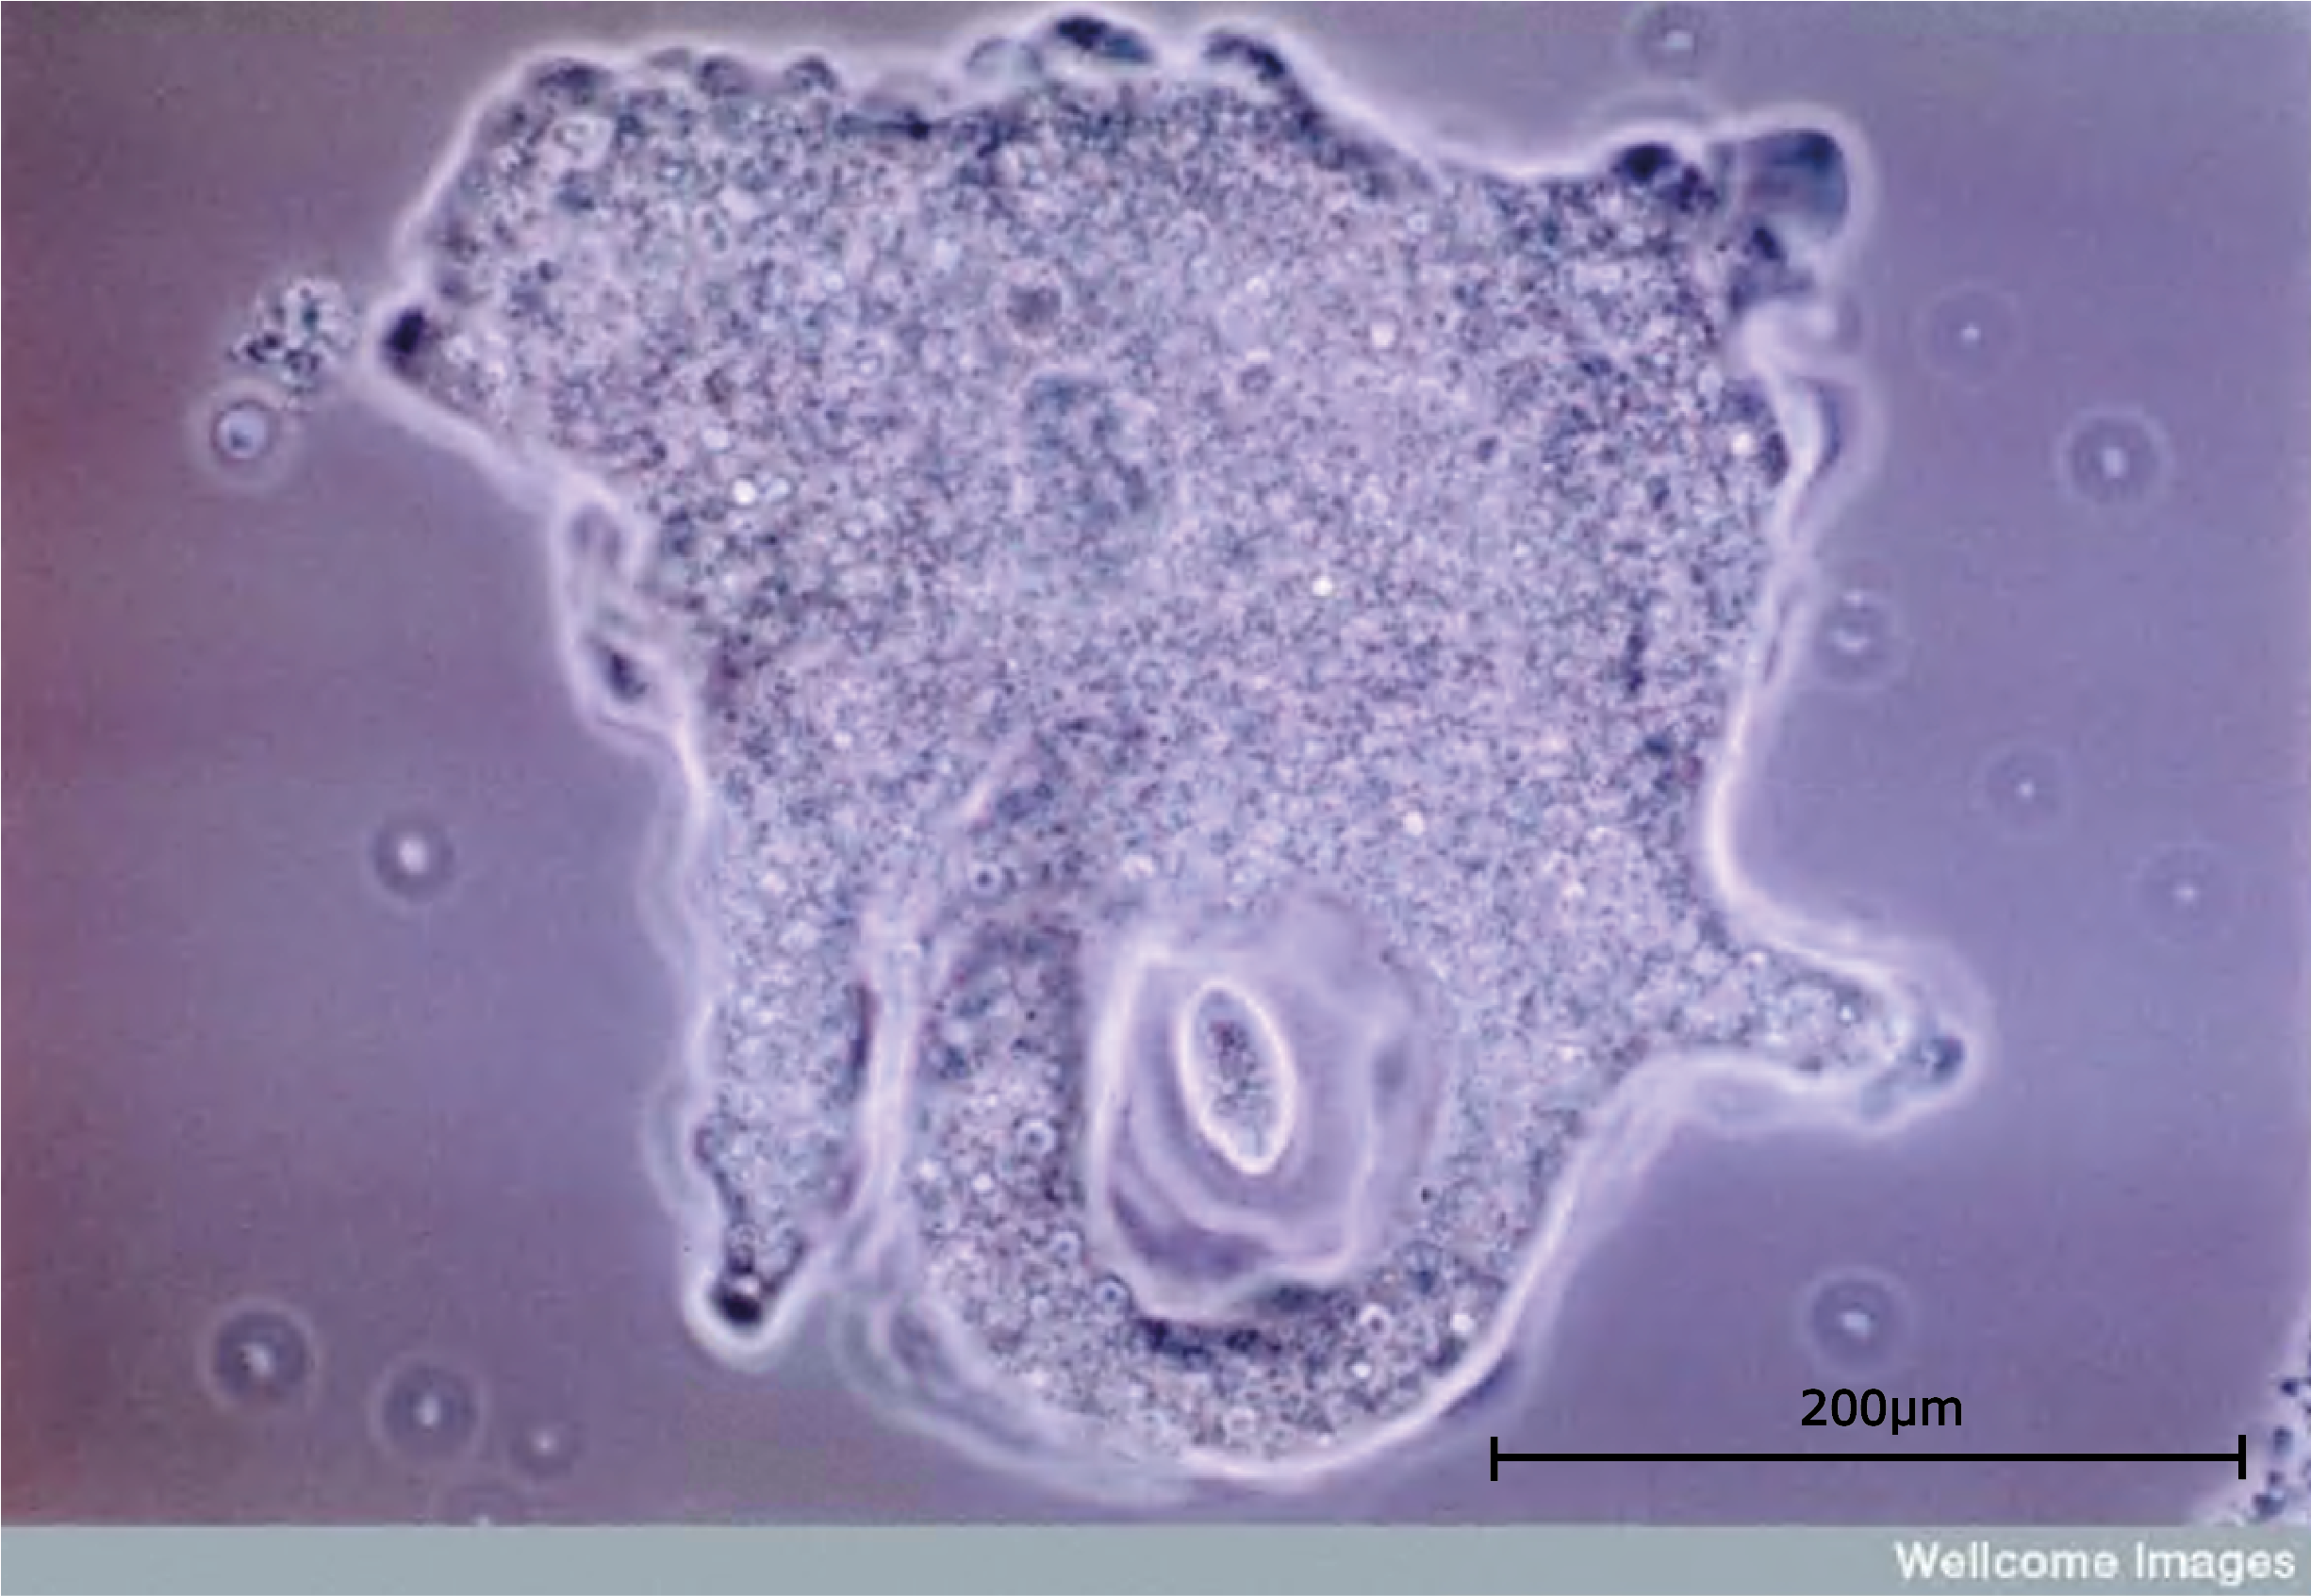

The protista consist of unicellular eukaryotic organisms which have a variety of methods of nutrition and reproduction. These single celled organisms come in an enormous range of shapes and lifestyles: from amoeba to diatoms, including plant-like cells that swim, animal-like cells that cannot move, cells that are shaped like bells or fans or shells - some may even be grouped into colonies. Within the protista are organisms which make up the greater part of the plankton of the oceans, and a few which cause some of the most serious diseases to affect the human race. In some ways the kingdom of the protista contains all the organisms which scientists are not able to classify into one of the other kingdoms.

The protozoa are one group of the protista and it is largely members of the protozoa that cause human diseases. They all act as parasites, and many of them involve other species for part of their life cycle, which is how they move from host to host. Human diseases caused by protozoa include: